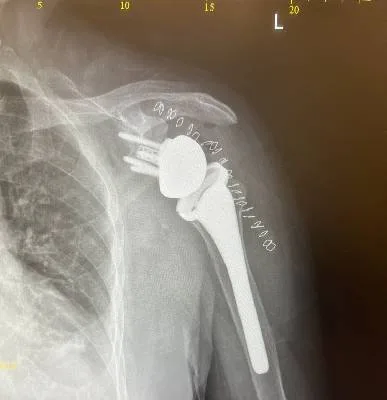

I had shoulder surgery done by Dr. Haytham Elkhatib using a minimally invasive arthroscopic technique. The recovery went very smoothly, and I’m really happy with the results. His team took great care of me during and after the procedure, and the physiotherapy and follow-up treatment were excellent. It’s been two months now, and I feel so much better — my shoulder is working normally again, and I’ve truly got my life back. I’m very thankful to Dr. Haytham and his team for their amazing care.